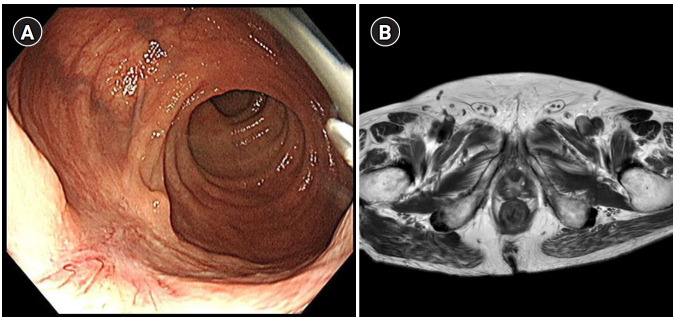

对于新辅助治疗后达到临床完全缓解(cCR)的局部晚期直肠癌患者,非手术治疗,特别是观察和等待(WW)策略,已成为全肠系膜切除术的替代方案。本文综述了与根治性手术相比,WW相关的肿瘤预后、功能和生活质量益处、诊断挑战和监测要求。来自随机试验和国际登记的证据表明,如果严格的选择标准和强化监测维持3至5年,WW提供与手术相当的总生存率和无病生存率。15%-40%的患者会出现局部再生,最常见的是在24个月内,但挽救性手术在90%以上的病例中是治愈的,并恢复肿瘤等效性。然而,远处转移在再生的患者中更为常见,这强调了早期发现的重要性和优化全身治疗的必要性。cCR的准确测定仍然是主要的限制;直肠指检、高分辨率磁共振成像和内窥镜检查,即使结合使用,也不能可靠地排除显微残留疾病。总的新辅助治疗将cCR率提高到30%-60%,并扩大了WW候选者的范围,但也加强了对标准化反应定义和监测算法的需求。只要多学科团队确保严格的反应评估和终身监测,WW在不影响精心挑选的患者生存的情况下提供器官保存和生活质量改善。未来在影像学、分子生物标志物和个体化风险分层方面的进展有望进一步提高WW的安全性,并将适用范围扩大到更广泛的患者群体。

Non‑operative management, particularly the watch and wait (WW) strategy, has emerged as an alternative to total mesorectal excision for selected patients with locally advanced rectal cancer who achieve a clinical complete response (cCR) after neoadjuvant treatment. This narrative review examines oncologic outcomes, functional and quality‑of‑life benefits, diagnostic challenges, and surveillance requirements associated with WW compared to radical surgery. Evidence from randomized trials and international registries indicates that WW provides overall and disease-free survival rates comparable to those of surgery, provided that stringent selection criteria and intensive surveillance are maintained for 3 to 5 years. Local regrowth occurs in 15%-40% of patients-most commonly within 24 months-but salvage surgery is curative in over 90% of cases and restores oncologic equivalence. Nevertheless, distant metastasis is more frequent in patients who experience regrowth, underscoring the importance of early detection and the need for optimized systemic therapy. Accurate determination of cCR remains the primary limitation; digital rectal examination, high‑resolution magnetic resonance imaging, and endoscopy, even when combined, cannot reliably exclude microscopic residual disease. Total neoadjuvant therapy increases cCR rates to 30%-60% and expands the pool of WW candidates, but also intensifies the need for standardized response definitions and surveillance algorithms. WW offers organ preservation and quality‑of‑life improvements without compromising survival in carefully selected patients, provided that multidisciplinary teams ensure rigorous response assessment and lifelong monitoring. Future advances in imaging, molecular biomarkers, and individualized risk stratification are expected to further enhance the safety of WW and expand eligibility to a broader patient population.